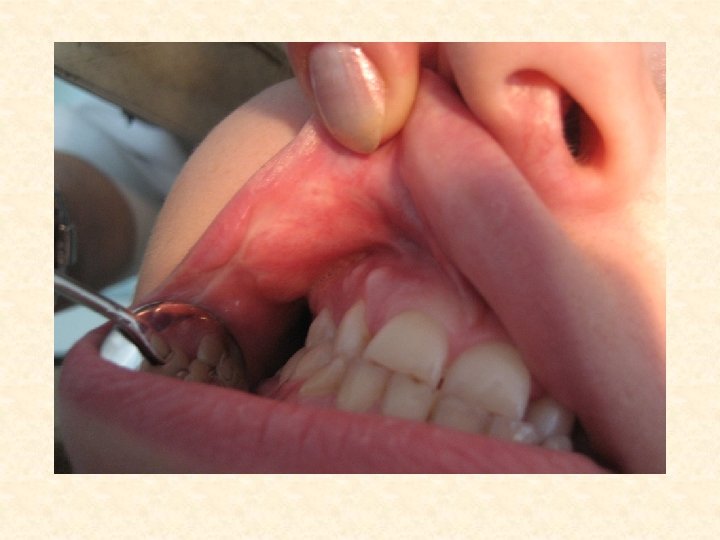

Контактные стоматиты • Являются наиболее частой формой поражения СОПР при аллергии. Они могут возникать при использовании любых медикаментозных препаратов. • Жалобы: жжение, зуд, сухость во рту, боль при употреблении пищи. • Общее состояние больных, как правило, не нарушается. • Объективно: гиперемия и отек СОПР, на боковых поверхностях языка и щеках по линии смыкания зубов четко проявляются отпечатки зубов. Язык гиперемирован, ярко красного цвета. Сосочки могут быть гипертрофированы или атрофированы. Одновременно может протекать катаральный гингивит. • Диф. диагностика: подобные изменения при патологии ЖКТ, гипо и авитаминозах С, В 1, В 6, В 12, эндокринных нарушениях, при сахарном диабете, патологии ССС, грибковых поражениях.

Контактный стоматит